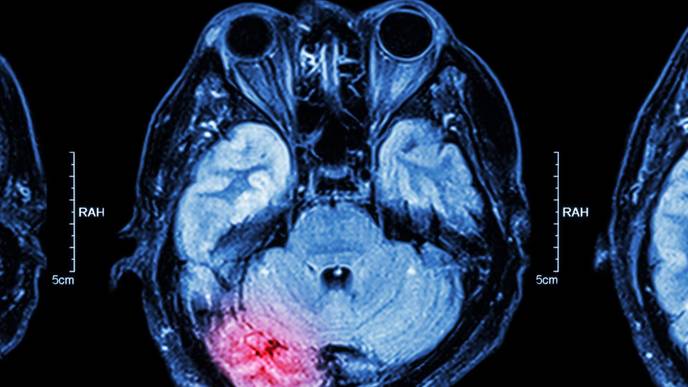

The HBOT protocol included 60 two-hour sessions in a hyperbaric chamber. During each session, participants alternated between breathing pure oxygen at twice the normal atmospheric pressure and regular air, cycling every 20 minutes. This alternation was designed to stimulate tissue healing by creating fluctuations in oxygen levels. Functional MRI imaging revealed improved connectivity in brain networks among HBOT participants, accompanied by significant reductions in PTSD symptoms. In contrast, no changes were observed in the placebo group, either clinically or in brain imaging.